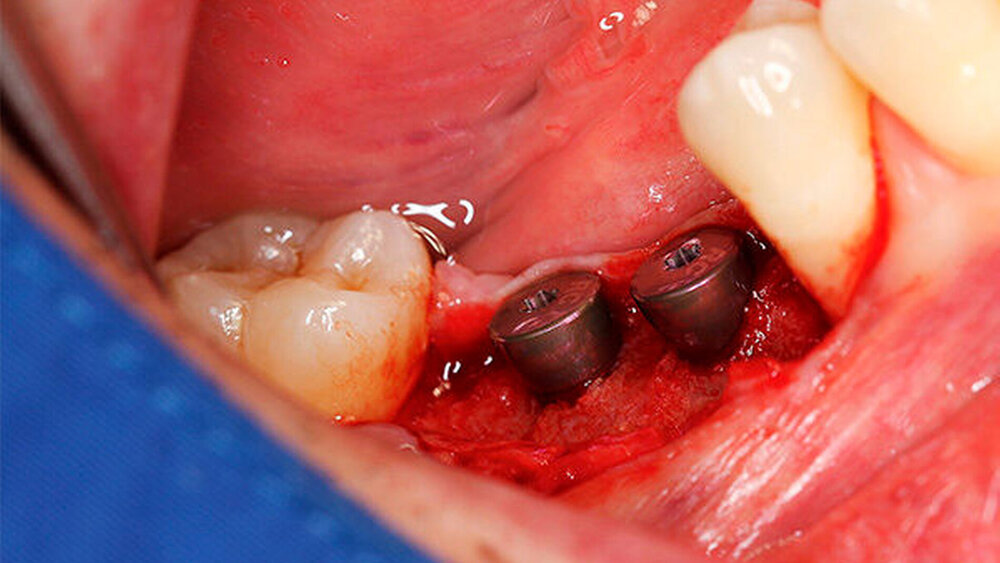

Ein 29-jähriger Patient stellte sich mit einer massiven Alveolarkammatrophie im rechten Unterkiefer in unserer Praxis vor. Diese lag in langen Jahren der Zahnlosigkeit begründet. Eine Beckenkammaugmentation kam für den Patienten nicht in Betracht. Dennoch wünschte er die Versorgung mit festsitzendem Zahnersatz. Nach ausführlicher Beratung entschied sich auch dieser Patient für eine Augmentation mit einem patientenindividualisierten allogenen CAD/CAM-gefertigten Knochenblock. Die DICOM-Daten des Unterkiefer-DVTs wurde an die Firma Zimmer gesendet, und es erfolgten wie im oben beschriebenen Fall eine virtuelle Planung und das virtuelle Design des allogenen Knochenblocks anhand der geplanten Implantatpositionen. Nach der üblichen Kontrolle und Freigabe des Chirurgen erfolgte die eigentliche Fertigung und Übersendung des Knochenblocks in die Praxis. Die Augmentation erfolgte auch in diesem Fall in Vollnarkose unter antibiotischer Abschirmung perioperativ mit Ampicillin. Die Schnittführung im Unterkiefer unterscheidet sich von der Sockelschnittführung im Oberkiefer aufgrund der Anatomie (N. mentalis). Auch bei diesem Patienten wurde eine tief im Vestibulum liegende bogenförmige Inzi‧sion durchgeführt, jedoch ohne die vertikalen Entlastungen. Nach streng subperiostaler Präparation erfolgte die Darstellung des N. mentalis. Die Vorbereitung des Spenderbetts sowie die Wässerung, Einpassung und Befestigung des allogenen Knochenblocks gestalteten sich wie im Fallbeispiel 1. Die Heilzeit des Knochenblocks dauerte ebenfalls sechs Monate. Zwei Implantate (Straumann) wurden nach krestaler Schnittführung in Lokalanästhesie eingebracht und heilten subgingival binnen drei Monaten ein. Aufgrund des massiven Volumenzuwachses war auch ebenfalls eine Vestibulumplastik im Zuge der Implantatfreilegung notwendig. Das Prozedere verlief ebenfalls wie im Fallbeispiel 1. Das freiliegende Gewebe wurde mit einer Kollagenmatrix abgedeckt. Dadurch konnte die Breite der befestigten Gingiva deutlich verbreitert werden.